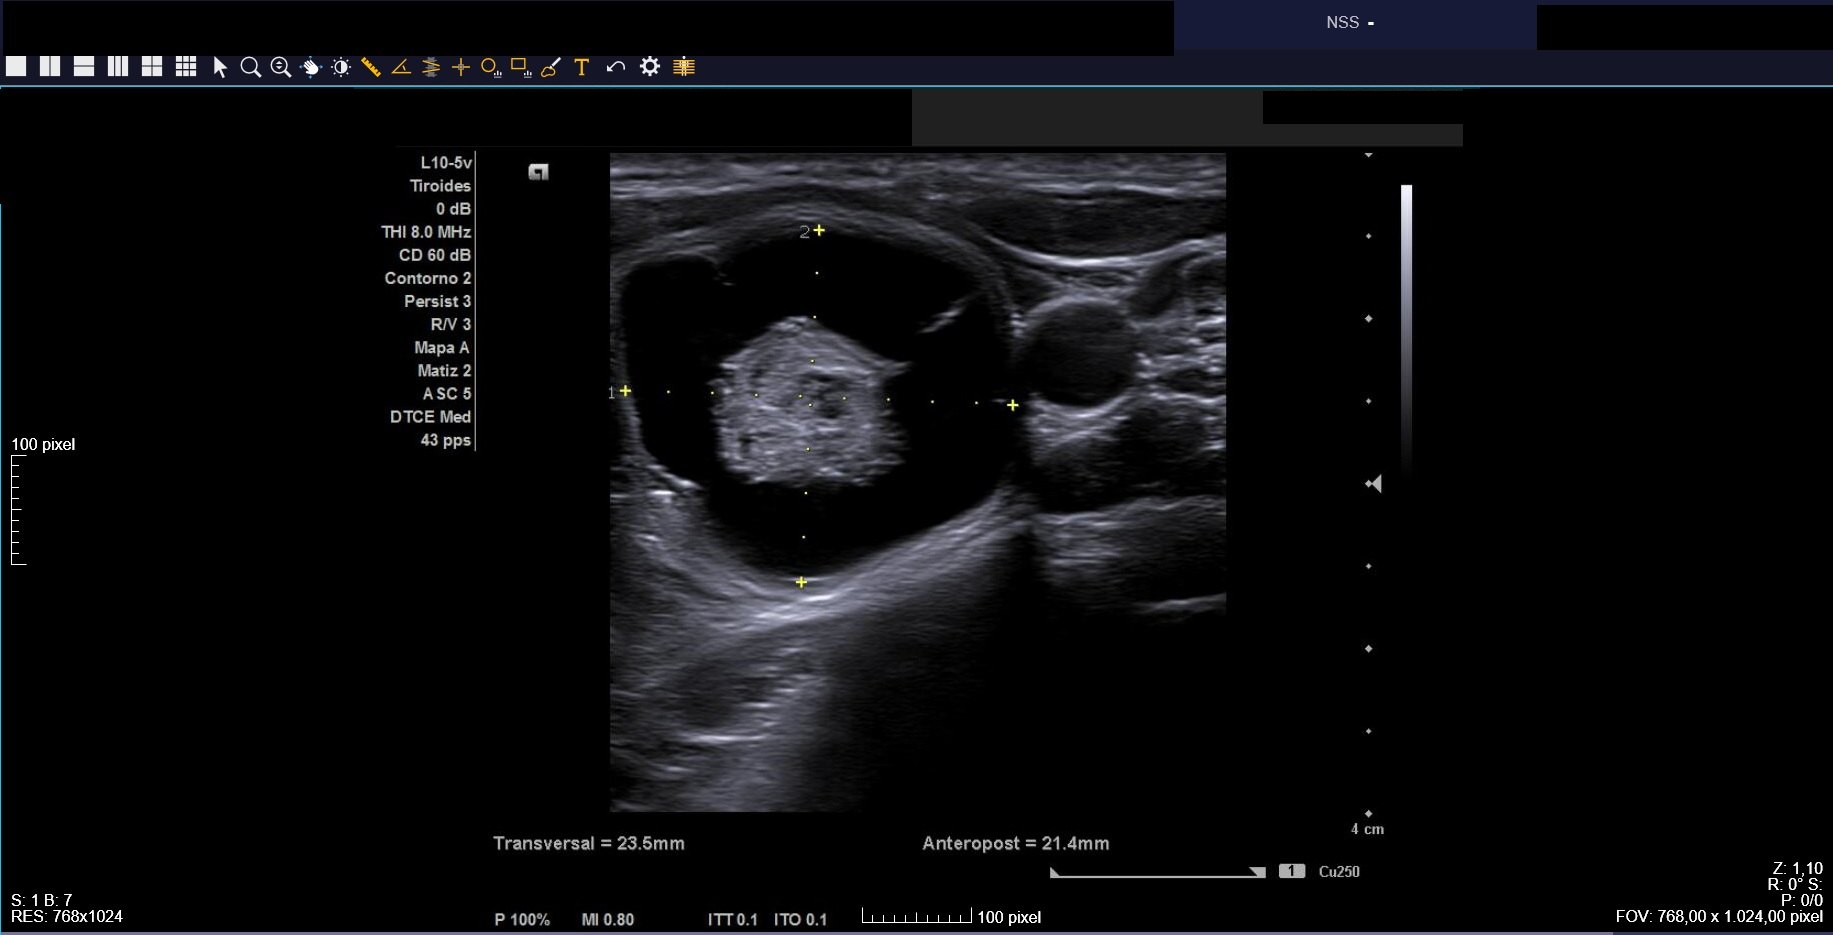

Ecografía clínica: tiroides de tamaño normal con ecoestructura homogénea. En lóbulo tiroideo izquierdo nódulo de 3 cm, anecoico, márgenes bien definidos con imagen hiperecoica en su interior (Imágenes 1, 2 y 3).

Citamos para seguimiento clínico-ecográfico dos meses después. El bulto había tenido una evolución fluctuante en tamaño pero habían reaparecido las molestias. Nueva ecografía (Imagen 4) confirmó nódulo de características similares a las iniciales, de tamaño ligeramente inferior (2,1 x 2,3 cm). Se observaban focos ecogénicos puntiformes y ecogenicidad indeterminada (TIRADS=4).